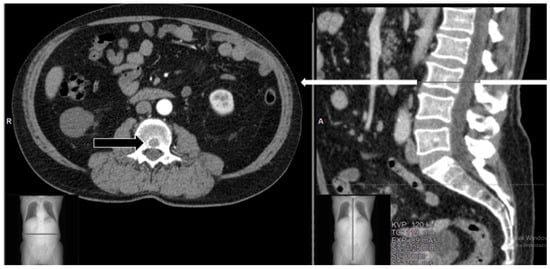

4. Case Series